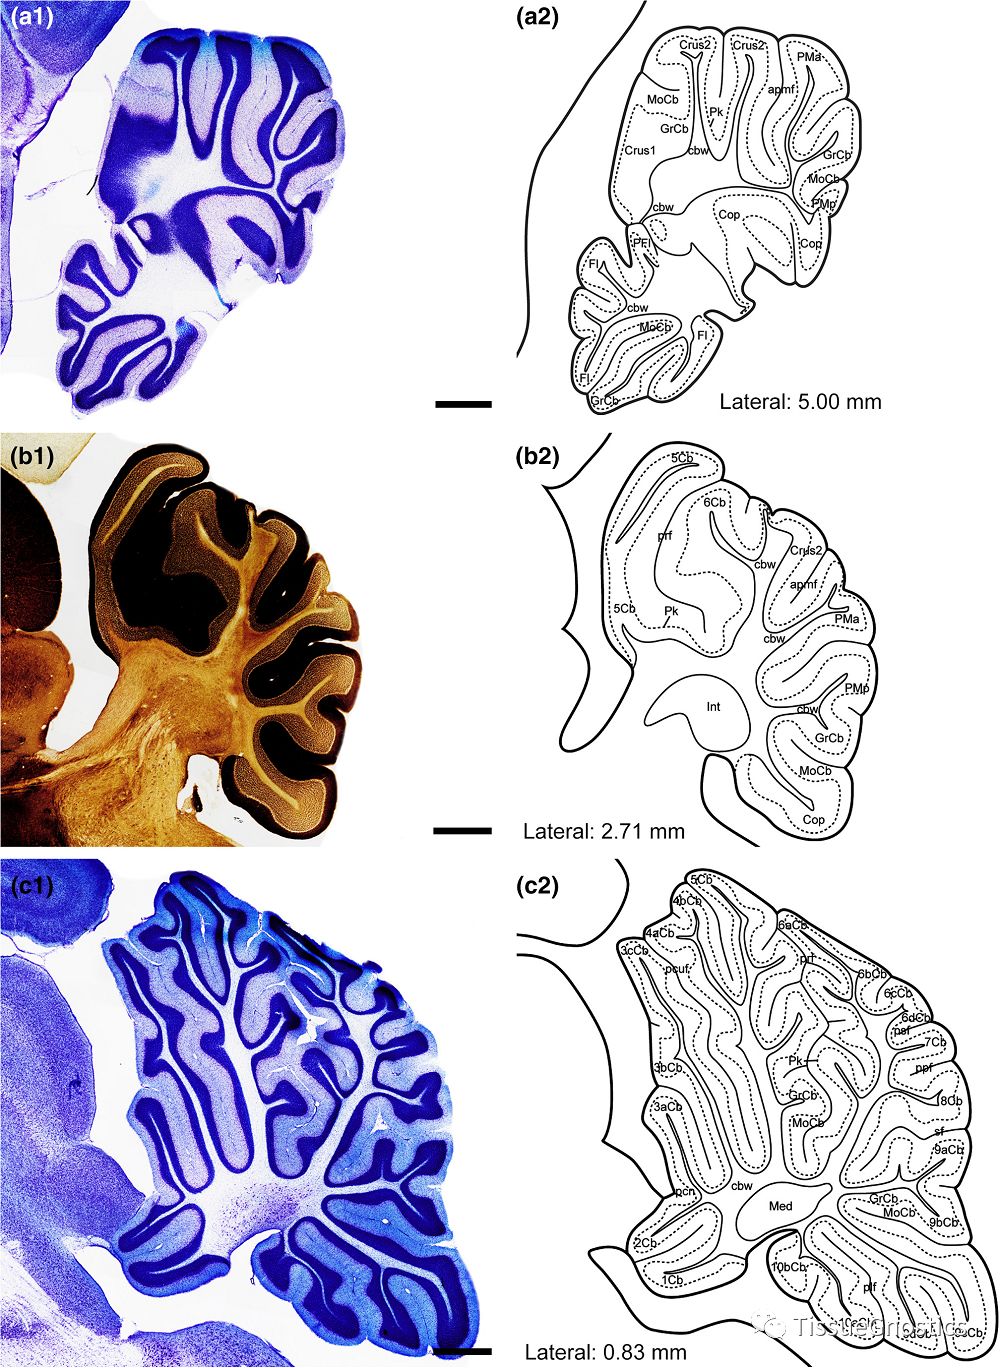

四川华西医院精神病学实验室和心理健康中心的专家们采用尼氏(Nissl staining)染色和AChE染色的免疫组化样本研究树鼩小脑的解剖学特征。由于小脑皮质呈现层状结构,所以将小脑的形态学特征在冠状面、矢状面和横断面进行描述;并对浦肯野细胞层中calbindin immunoreactive(-ir)细胞的分布进行阐述。

图4:树鼩从内侧到外侧的小脑亚区AChE染色,Nissl染色切片(a1,b1,c1)。冠状面的小脑亚区的一般形态(a2,b2,c2)。